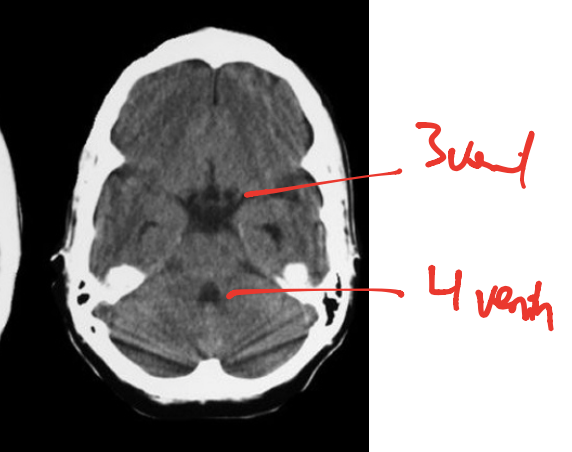

what is red dot? why is it squashed

3rd ventricles, due to the thalamus on either side!

4th ventricle _smaller_ than 3rd>> u can tell there is a blockage in aqueduct